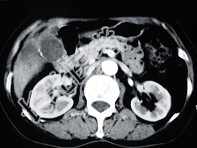

- 单项选择题女,66岁, 右上腹痛,发热伴有黄疸两月余, 消瘦、纳差,影像检查如图, 最可能的诊断为( )

A、胆囊癌及原发性肝癌

B、肝内胆管细胞癌

C、胆囊结石及脂肪肝

D、胆囊结石及肝血管瘤

E、胆囊癌肝转移